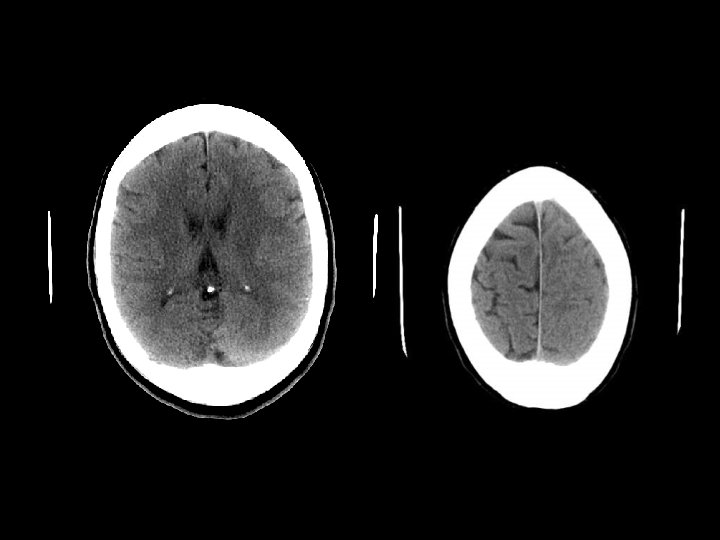

DIFFUSE AXONAL INJURY n Jarang terdeteksi pada CT ( 20% dari lesi DAI berupa perdarahan) n MRI: T 1, T 2 GRE, SWI

DAI n Akibat akselerasi / deselerasi terhadap white matter + hipoksia n Patients have severe LOC at impact n Grade 1: kerusakan axonal pada WM saja -67% n Grade 2: WM + corpus callosum (posterior > anterior) – 21% n Grade 3: WM + CC + brainstem

DAI n Beberapa jam : n Perdarahan dan robekan jaringan n Axonal swellings n Axonal bulbs n Beberapa hari/minggu : clusters of microglia and macrophages, astrocytosis n Beberapa bulan/tahun : Wallerian degeneration